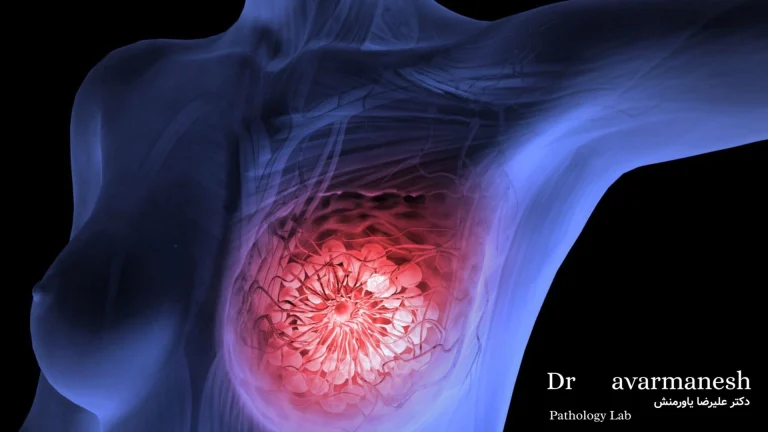

تظاهرات بالینی و علائم سرطان سینه

تظاهرات بالینی

تظاهرات بالینی به مجموعهی نشانهها و علائمی گفته میشود که فرد تجربه میکند یا پزشک در معاینه و تصویربرداری مشاهده میکند. در این نوع تومور، این تظاهرات میتوانند از تغییرات بسیار جزئی تا علائم آشکار و پیشرفته متفاوت باشند.

علائم سرطان سینه چگونه است؟

علائم این بیماری معمولاً بهتدریج ظاهر میشوند و در مراحل اولیه ممکن است بدون درد یا نشانهی واضح باشند.

- وجود توده یا غده در پستان:

شایعترین علامت این بیماری، توده یا غده در یکی از پستانها است.

این توده معمولاً سفت، با لبههای نامنظم و غیرقابلحرکت است.

در نوع خوشخیم، توده نرمتر و متحرکتر است، اما در تودههای بدخیم معمولاً به بافت اطراف میچسبند.

در مراحل اولیه، توده ممکن است کوچک و بدون تغییر در پوست یا نوک پستان باشد، اما در صورت پیشرفت بیماری اندازهی آن افزایش مییابد و ممکن است به بافتهای اطراف گسترش پیدا کند. - تغییر در شکل یا اندازهی پستان:

گاهی یکی از پستانها بزرگتر یا سفتتر بهنظر میرسد یا تقارن طبیعی آنها از بین میرود. - تغییرات پوستی:

تغییرات پوست از علائم مهم و هشداردهنده در این بیماری هستند.

در این حالت ممکن است پوست دچار فرورفتگی، چروکیدگی یا ضخیم شدن شود.

گاهی ظاهر پوست شبیه پوست پرتقالی (peau d’orange) میشود که نشاندهندهی درگیری عروق لنفاوی پوست است.

در برخی بیماران، زخم یا التهاب پوست پستان نیز ممکن است دیده شود؛ این حالت معمولاً در مراحل پیشرفتهتر بیماری یا در نوع التهابی آن مشاهده میشود. تغییرات نوک پستان: